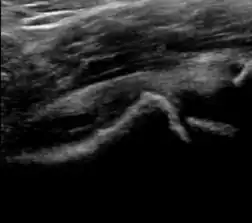

Ultrasound

Ultrasound is the first-choice technique for diagnosis of newborns hip dysplasia. In experienced hands with appropriate technology, ultrasound can also be useful during the first year of life. Some European healthcare systems encourage universal ultrasound screening in neonates between the sixth and eighth weeks. Although it shows higher initial costs caused, it leads to significant reduction in the total number and overall costs of dysplastic hips undergoing operative and nonoperative treatment.[1]

Ultrasound allows categorizing pediatric hips, according to Graf’s criteria, in four main types: normal, immature, and dysplastic (subluxed and dislocated). This classification is based on measurements of the acetabular inclination angle (alpha), cartilage roof angle (beta), and infant age. The femoral head coverage can also be determined by dividing the length of the femoral head covered by the acetabular fossa and the diameter of the femoral head. Its lower normal limits are 47% for boys and 44% for girls (Figure 11).[1]

Figure 11:

-

Useful ultrasound measures in neonatal hip sonography, alpha and beta angles.[1] -

Measurement of femoral head coverage.[1]

In a recent study, including newborns with high clinical suspicion for DDH (Ortolani/Barlow test, asymmetry in abduction of 20° or greater, breech presentation, leg-length discrepancy, and first-degree relative treated for DDH), hip sonography led to a change in clinical diagnosis in 52% of hips and to a change in management plan in 32% of hips. It obviated further follow-up in 23%, strengthening its role as an important technique reassuring the clinical diagnosis.[1]

During childhood, ultrasound is a quick method to assess hip pain and quite often may be used to avoid use of irradiating techniques, such as radiography or CT. Ultrasound allows evaluation of joint effusion, synovial thickening and neovascularity, the bone/cartilage contour, and the femoral head-neck alignment. Although sonography is extremely sensitive in detecting increased synovial fluid, it is nonspecific and cannot be used with accuracy to determine the type of fluid. Transient synovitis of the hip, despite being the most frequent cause of pain in children between 3 and 10 years, remains a diagnosis of exclusion. It usually shows anechoic fluid, but echogenic fluid can also be found. The effusion is considered pathologic when it is measured at >2 mm in thickness. The differential diagnosis is wide, including osteomyelitis, septic arthritis, primary or metastatic lesions, LCPD, and SCFE. Discrimination from septic arthritis is challenging, often requiring joint aspiration. In septic arthritis, US is able to demonstrate a hip joint effusion, synovial thickening, and cartilage damage, although the appearances are nonspecific.[1]

A step between the head and the physis can be detected in children with SCFE, while abnormalities in the femoral head contour may suggest the presence of LCPD. In both cases, radiographs are mandatory to confirm diagnosis and severity (Figure 12).[1]

Figure 12:

Normal ultrasound appearance of the femoral head-neck junction. -

Joint effusion in transient synovitis of the hip. -

Flattening of the femoral head in a patient with Perthes disease. -

Step in the femoral head-neck junction in a patient with SCFE.